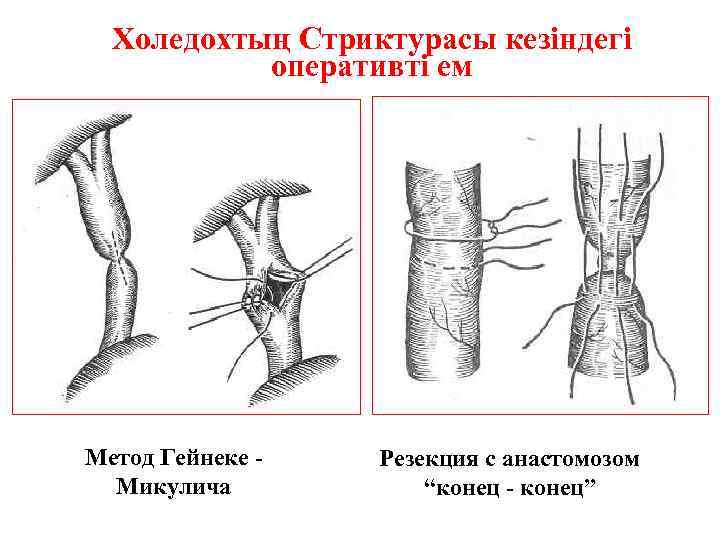

Холедохтың Стриктурасы кезіндегі оперативті ем Метод Гейнеке Микулича Резекция с анастомозом “конец - конец”